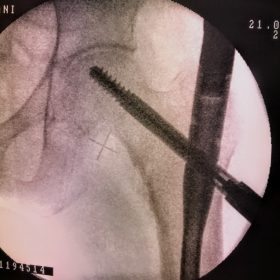

Υποκεφαλικό : Είναι ενδαρθρικό κάταγμα στον αυχένα του μηριαίου (το εσωτερικό του αρθρικού θυλάκου), το οποίο διακόπτει την αιμάτωση της κεφαλής του μηριαίου και οδηγεί σε μη πόρωση του κατάγματος (ΟΣΤΕΟΝΕΚΡΩΣΗ της Μηριαίας κεφαλής). Σε ασθενείς κάτω των 65 ετών αντιμετωπίζεται χειρουργικά με κοχλίωση στις πρώτες 12 ώρες. Τρείς βίδες σε σχήμα Τ με την βοήθεια τηλεόρασης διαδερμικά χωρίς διάνοιξη. Σε ασθενείς από 65-75 ετών γίνεται ολική αρθροπλαστική και σε ασθενείς άνω των 75 ετών αλλάζεται μόνο η κεφαλή χωρίς την αλλαγή της κοτύλης. Ο ασθενής περπατάει άμεσα μετεγχειρητικά στις 5 ώρες και εξέρχεται από το νοσοκομείο σε 1 -2 ημέρες. Στην κοχλίωση μπορεί να εξέλθει και την ίδια ημέρα.